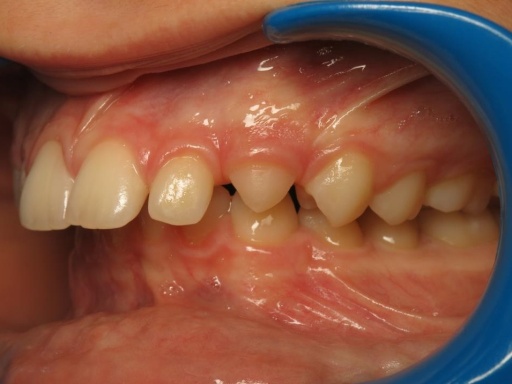

2 - Préparation orthodontique et résultat après chirurgie

Les photos supérieures montrent les arcades juste avant la chirurgie, avec un alignement complet et des axes dentaires physiologiques. La largeur de l’arcade maxillaire a été préparée pour permettre un emboîtement optimal après l’avancée mandibulaire. En bas, les photos post-opératoires montrent des arcades désormais coordonnées, avec une occlusion stable et harmonieuse, grâce à une préparation rigoureuse en amont de l’intervention chirurgicale.